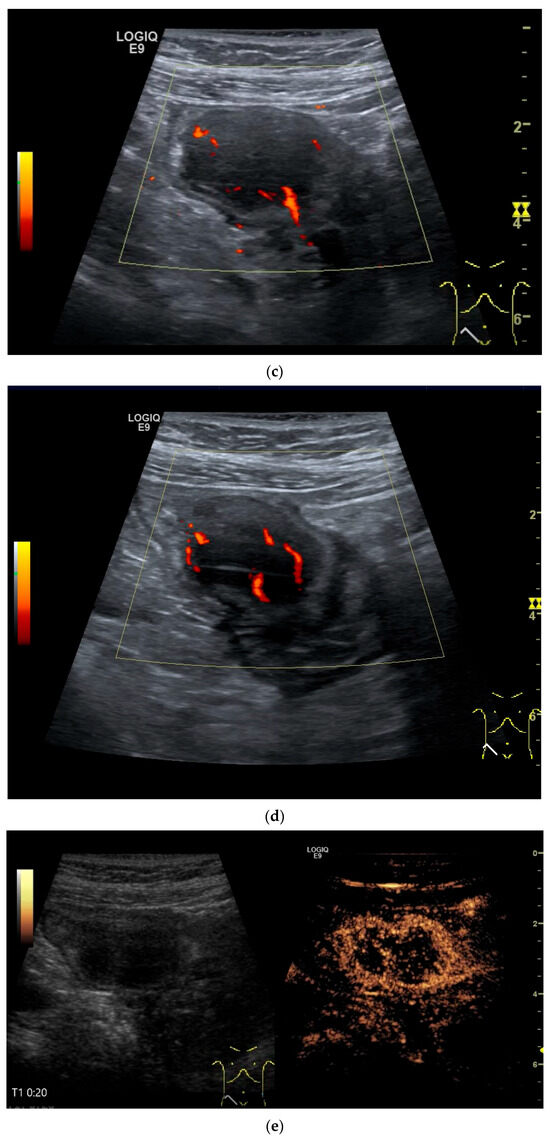

Figure 13.

Inflammatory fibroid tumor (Vanek’s tumor). In cases of unclear occult gastrointestinal bleeding, a smooth-edged oval hypoechoic mass measuring up to 30 mm in size can be seen in the terminal ileum. Examination with the abdominal sector transducer 1–5 MHz (a) and linear transducer 2–9 MHz (b). In power Doppler, a feeding vessel (c) and macro vessels in the mass (d) are visible. In CEUS with 2.4 mL SonoVue using a 9 MHz linear transducer, hyperenhancement is only visible at the edge in the arterial phase. Few vascular signals are visible in the lesion (e). The tumor remains hypoenhanced (f).